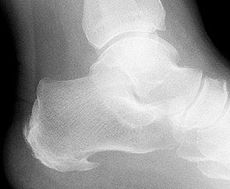

Der untere Fersensporn hat seinen Namen von dem im Röntgenbild häufig gut sichtbaren knöchernen Anbau am Plantarsehnenansatz im unteren Bereich des Fersenbeins. Man spricht auch von einem plantaren Fersensporn.

Nach der klinischen Untersuchung des Fersensporns kommen verschiedene bildgebende Verfahren zum Einsatz. Das Röntgenbild zeigt eine mögliche Fehlstellung oder Fehlbelastung der schmerzenden Ferse. Länge und Form des Fersenbeins sind wichtige Aussagen der Röntgenuntersuchung. Zusätzlich können Röntgenbilder im Stehen durchgeführt werden und über belastungsabhängige Fehlstellungen Aufschluss geben.